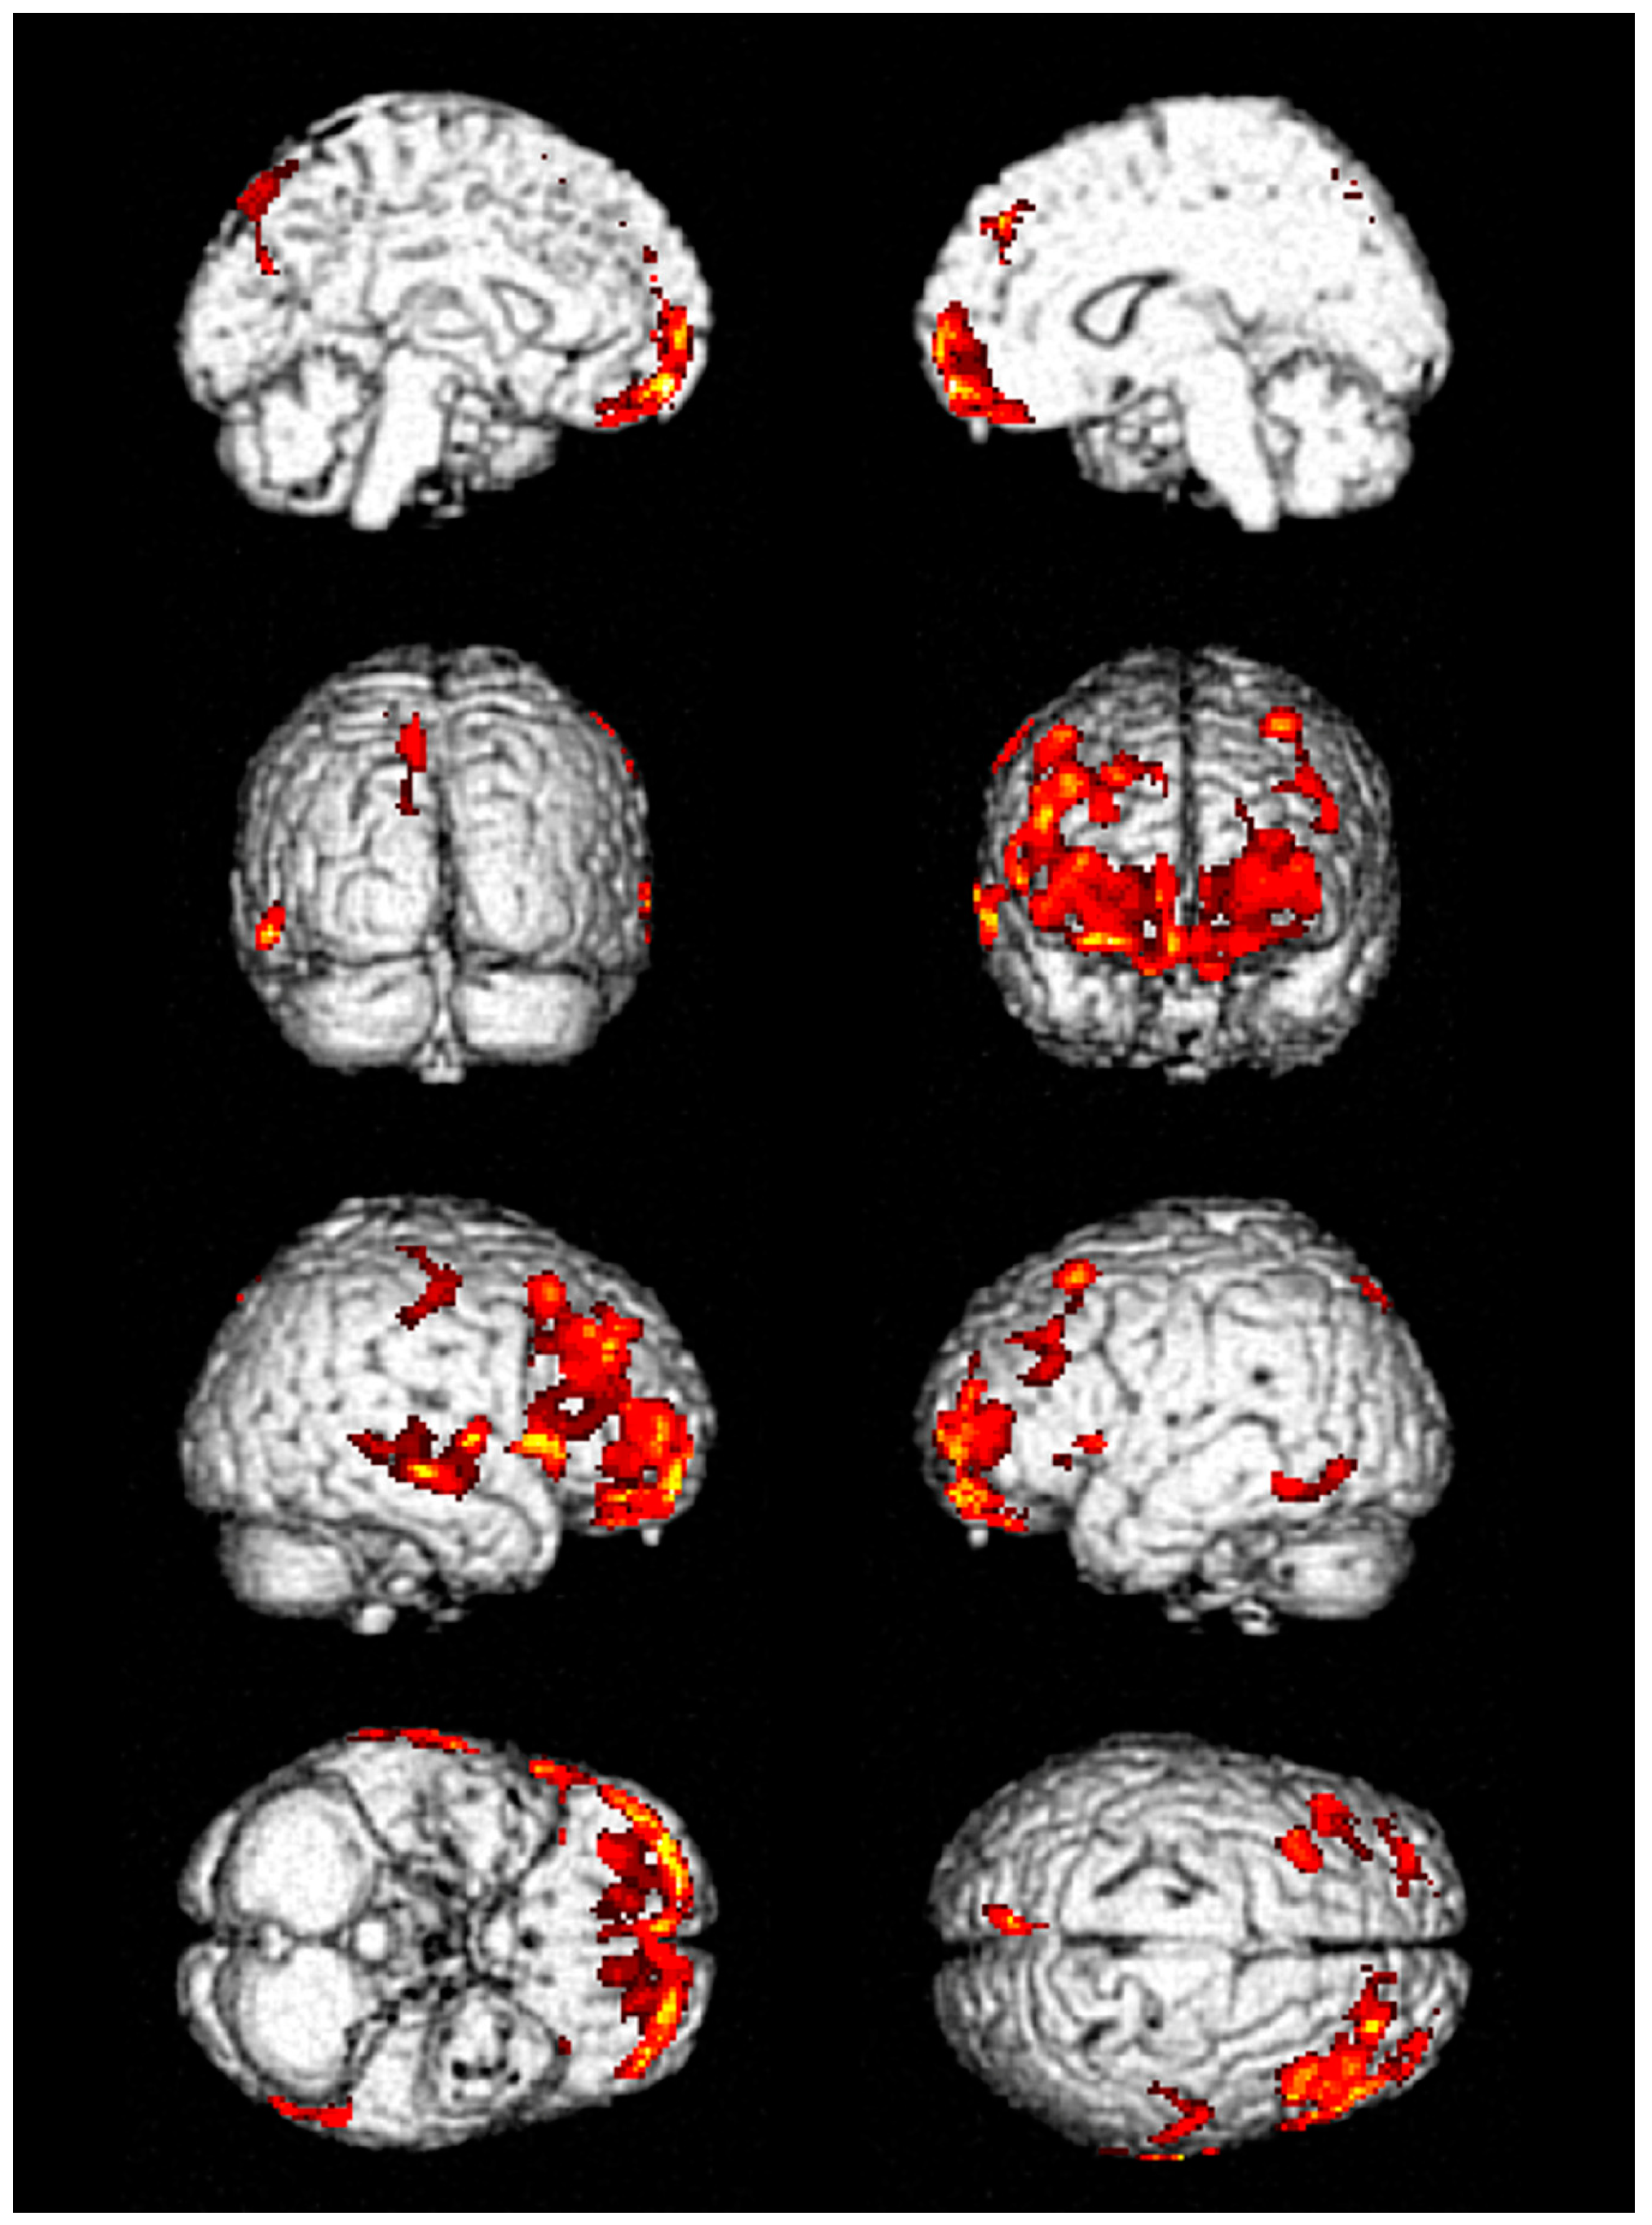

3. Results

| No. | FDG-PET Finding | Hospital Stay, Days | ICU Stay, Days | Seizure Duration, Days | F/U Duration, Months | ||

|---|---|---|---|---|---|---|---|

| Initial | Follow up (I) | Follow up (II) | |||||

| 1 | Decreased metabolic activity in frontal and temporal lobes | Improved but remained | Improved but remained | 53 | 41 | 6 | 12 |

| 2 | Decreased metabolic activity in frontal and temporal lobes | Improved | Improved | 6 | 3 | No | 3 |

| 3 | Decreased metabolic activity in frontal and temporal lobes | Not performed | Not performed | 14 | 7 | 2 | 6 |

| 4 | Decreased metabolic activity in inferior frontal lobe | Not performed | Not performed | 10 | 6 | 1 | 1 |

| 5 | Decreased metabolic activity in frontal lobe | Not performed | Not performed | 12 | 4 | 1 | 1 |

| 6 | Decreased metabolic activity in frontal and temporal lobes | Not performed | Not performed | 24 | 8 | 3 | 2 |

| 7 | Decreased metabolic activity in frontal and temporal lobes | Not performed | Not performed | 19 | 13 | 3 | 1 |

| 8 | Decreased metabolic activity in frontal and temporal lobes | Improved | Not performed | 9 | 3 | No | 2 |

| 9 | Decreased metabolic activity in frontal and temporal lobes | Not performed | Not performed | 11 | 5 | 2 | Loss |